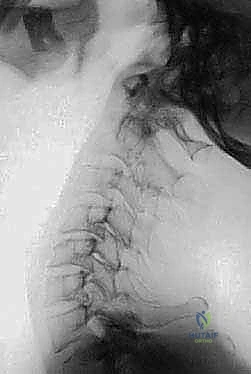

FIG 3 • E. Extension lateral radiographs demonstrate C1–2 instability in a patient with rheumatoid arthritis.